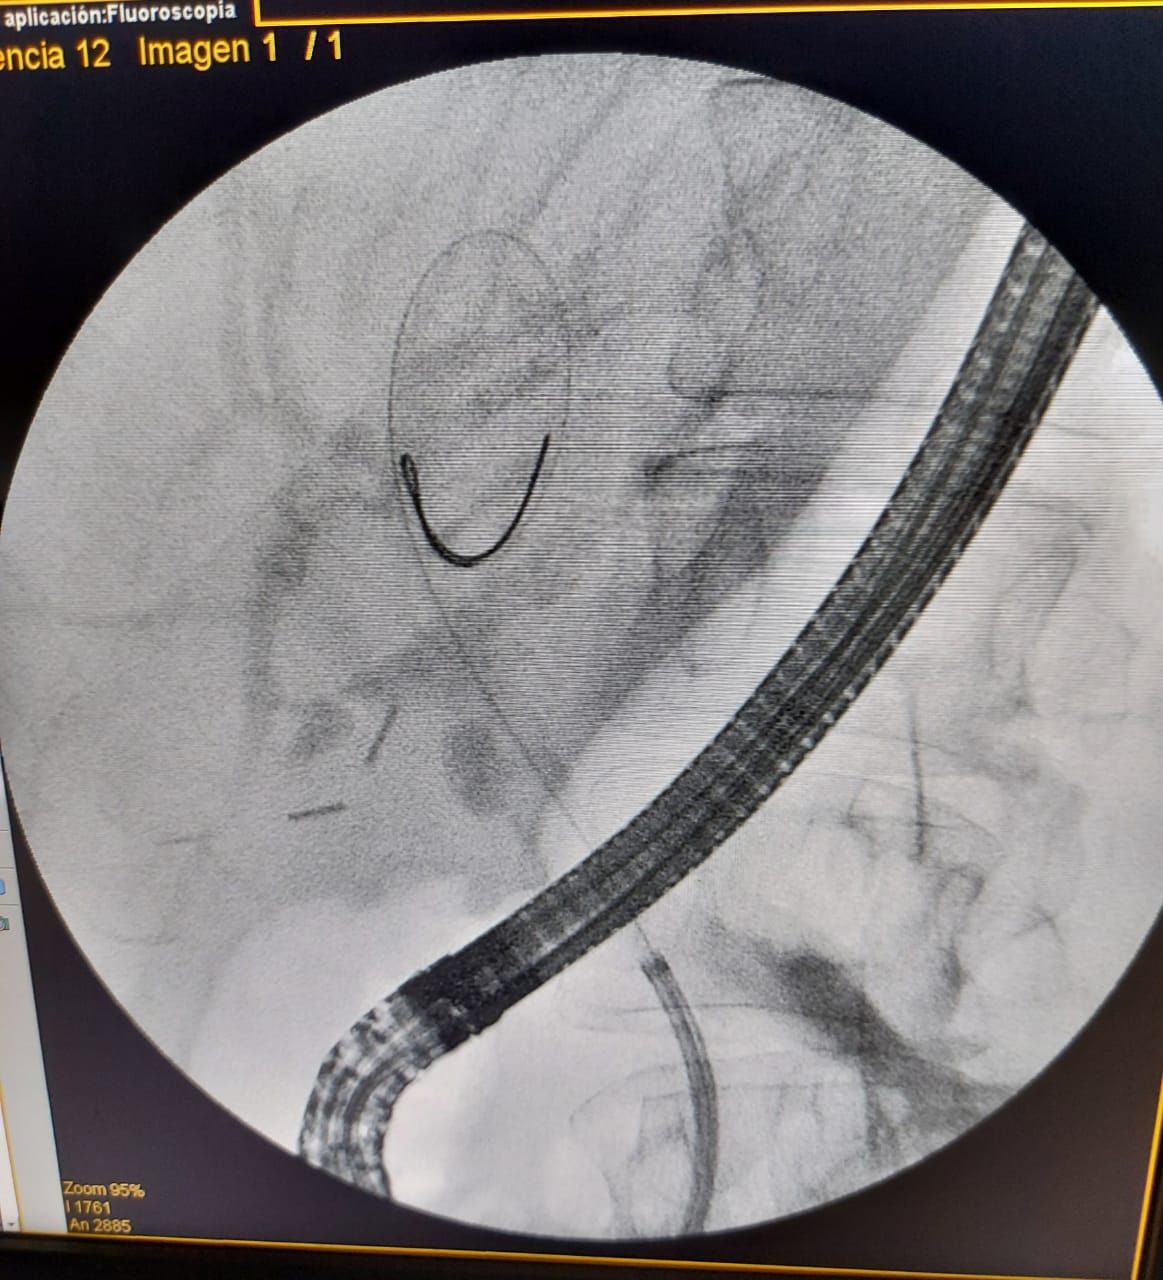

Se trata de un procedimiento denominado colangioscopia peroral y fue practicado por primera vez en la provincia el 1° de febrero, más precisamente en el Hospital Italiano. Esta técnica consiste en la introducción de un tipo de endoscopio llamado duodenoscopio hasta el conducto biliar, donde se despliega otro aparato más pequeño conocido como colangioscopio, con el que se realizará el diagnóstico por imagen. Ambas herramientas conforman el sistema digital Spyglass cuya tecnología permite este tipo de visualizaciones.

Jorge Isaguirre, Jefe del Centro de Endoscopía Avanzada del Hospital Italiano, explicó a MDZ que la colangioscopia peroral permite el acceso del duodenoscopio "entrando por la boca, pasando por el esófago y el estómago hasta el duodeno, más precisamente a los conductos biliares que se conectan con el hígado". Una vez que se llega a ese sector, añadió, "progresamos con otro endoscopio llamado colangioscopio, un endoscopio más fino que se introduce dentro de ese conducto biliar".

Otro avance muy importante que permite esta tecnología es la utilización de una pinza Spybite que permite realizar biopsias de forma no invasiva y que ayuda en la detección y mapeo de posibles tumores biliares.